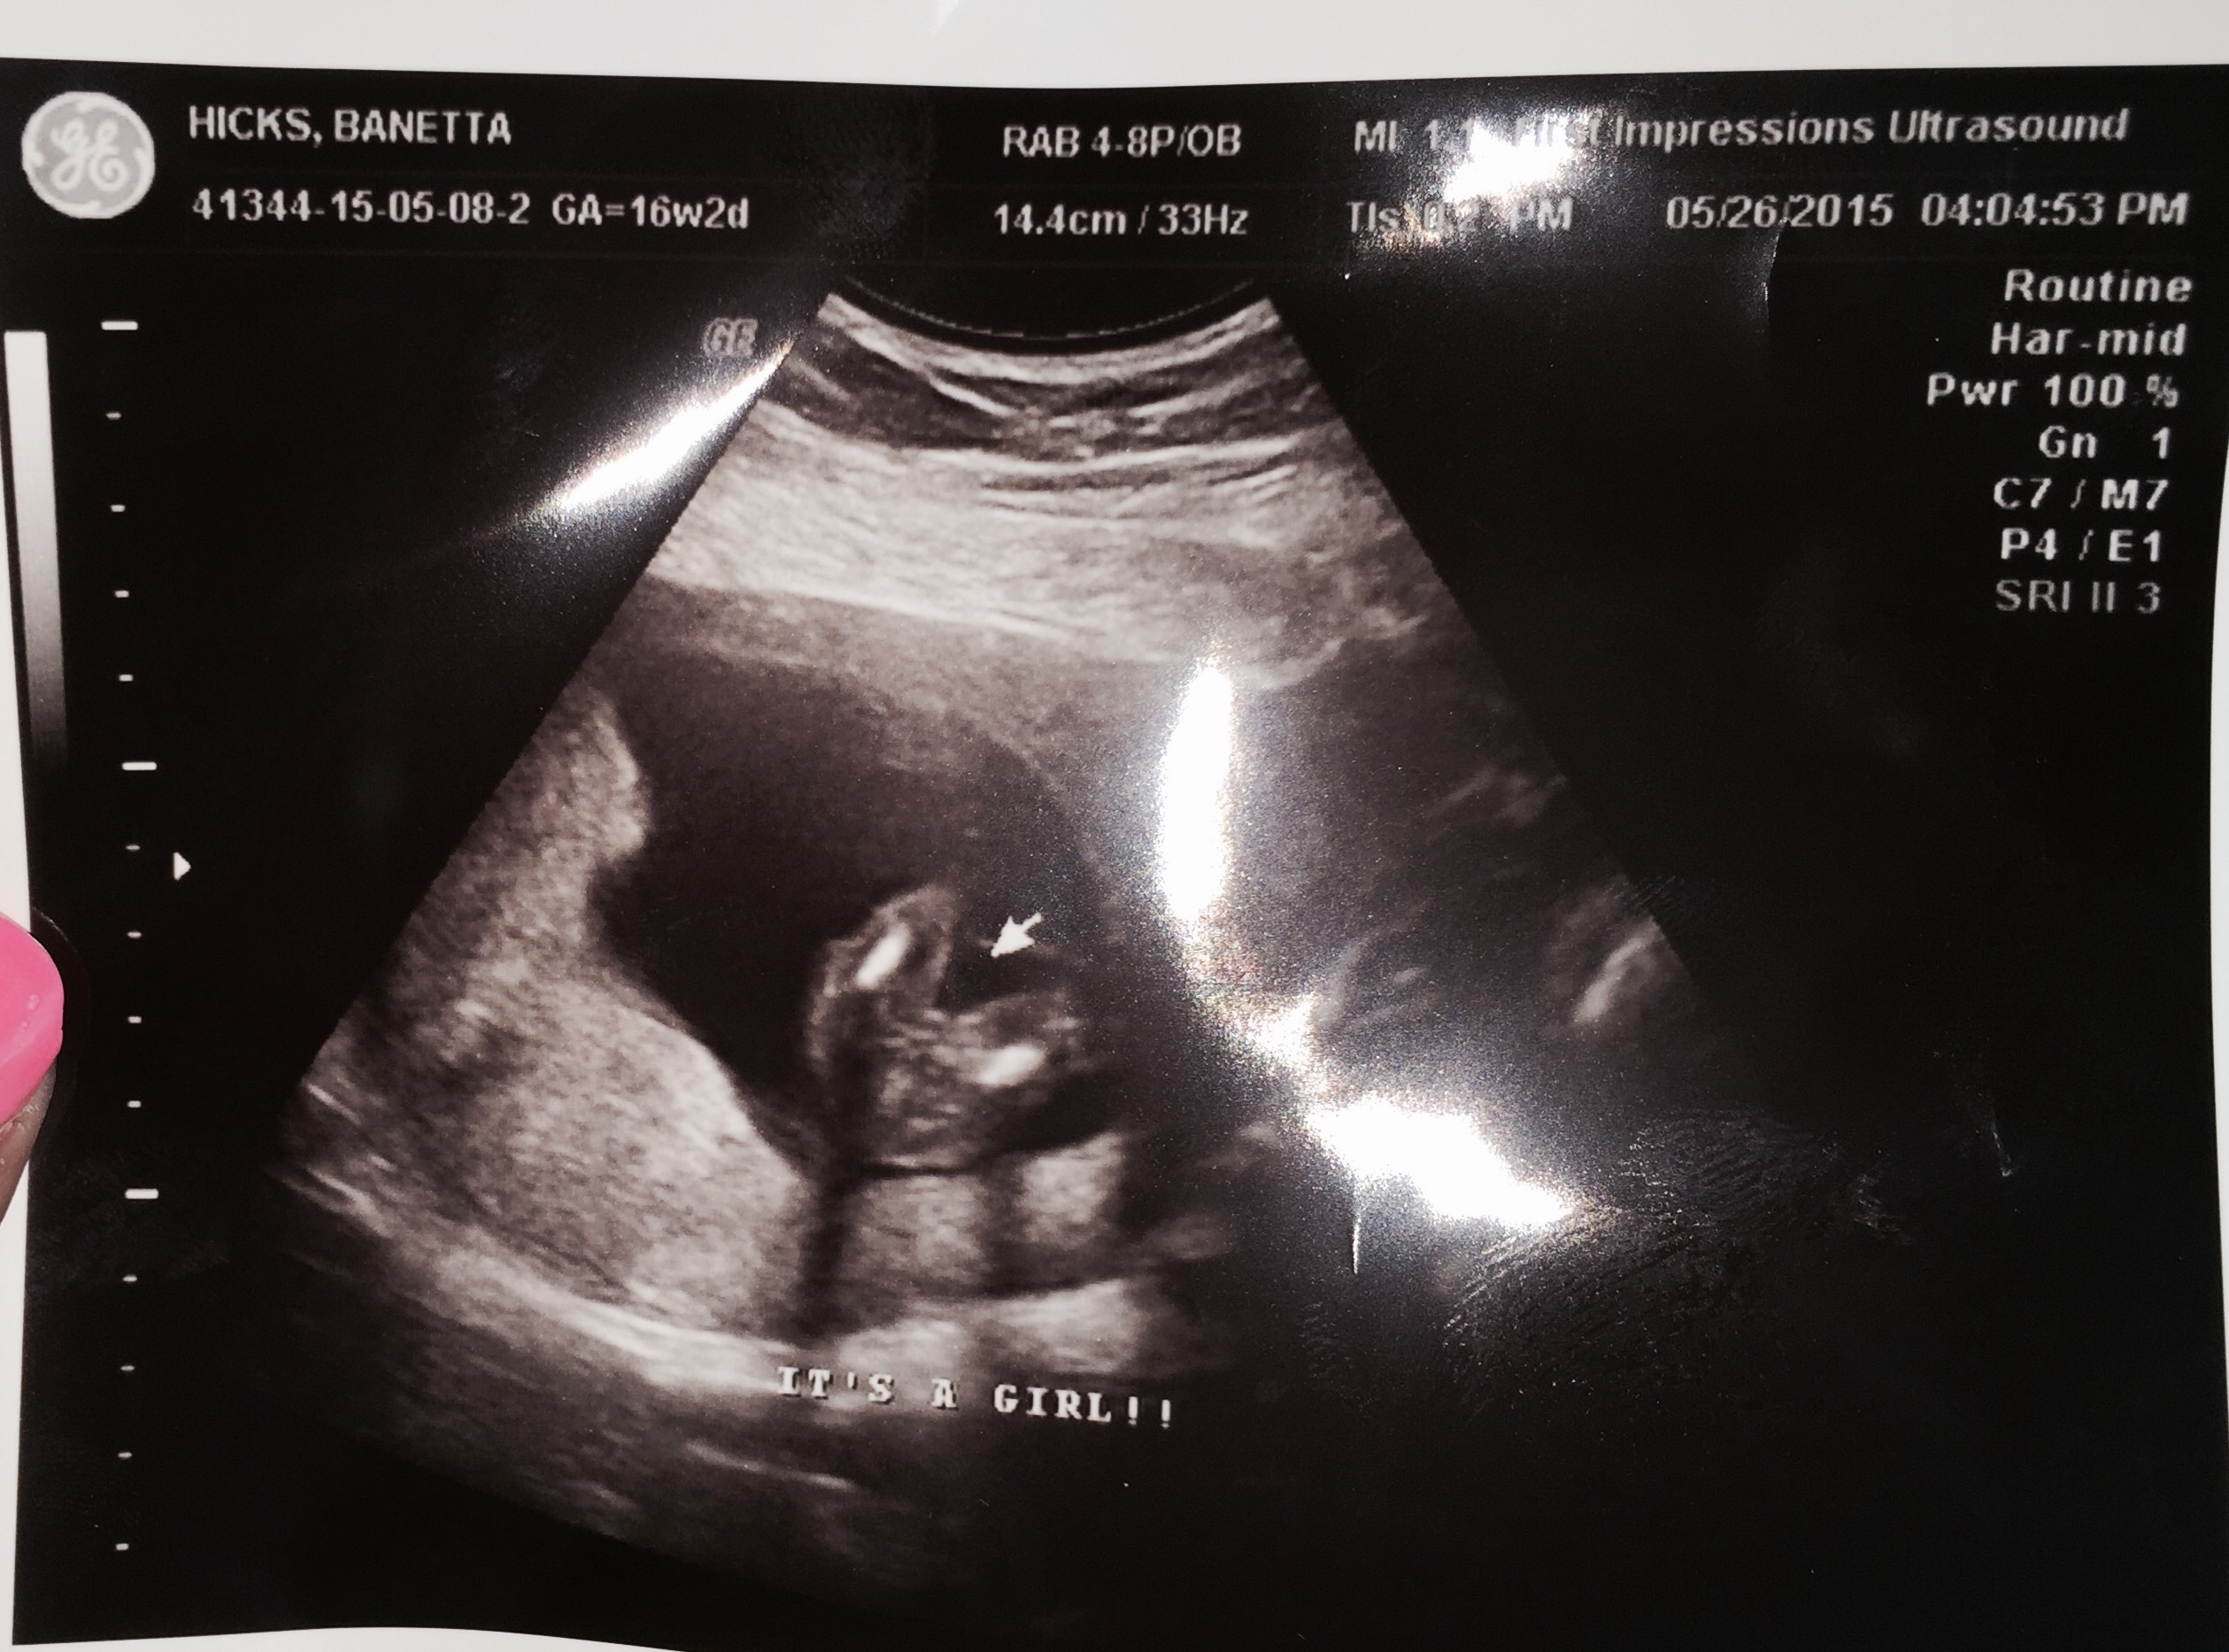

Just found out today 15 weeks! PINK! My 7 yr old daughter, Scarlett, was so excited she cried. We were thinking Penelope (penny)...but now hubby wants to look at ALL names again. Lol we will see